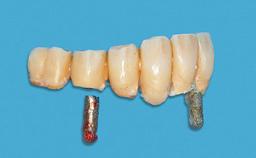

Replacement of an Upper Right Central Incisor with a Root Fracture, Early Placement of an RC Bone Level Implant, Variobase Abutment

Prosthesis Type FDP